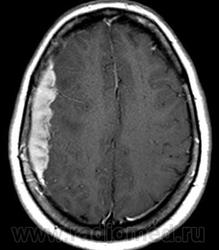

ГМ. СМ. Нейросаркоидоз. Саркоидоз на спинальном уровне. +

Нейросаркоидоз